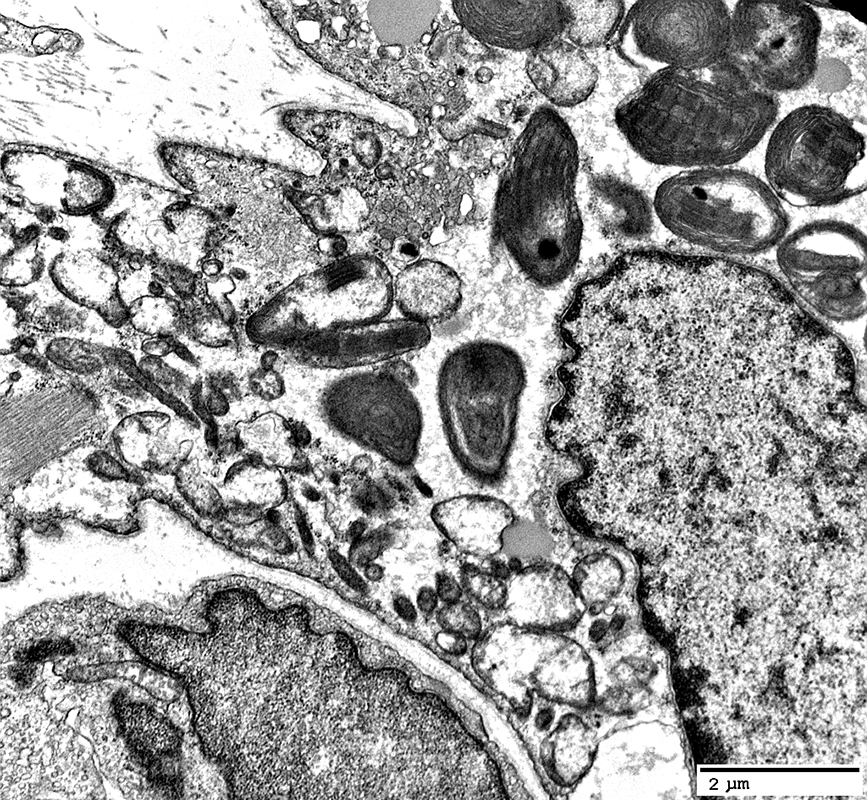

MNGIE: Muscle Ultrastructure

From: R Schmidt